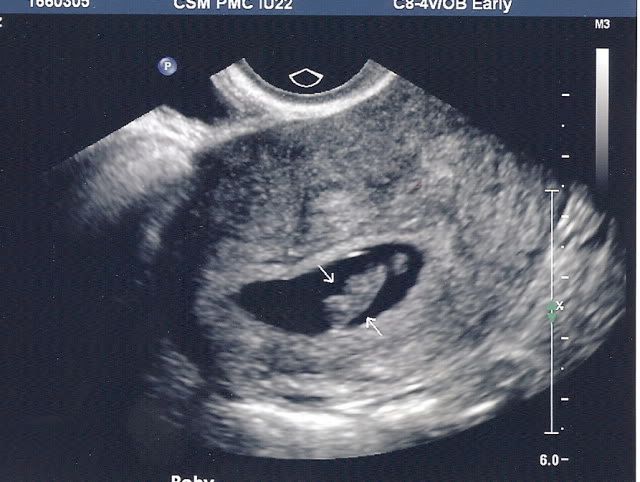

So I'll be joining the July Mommys with a due date of July 3rd. I am 8 weeks along today. I took a positive test about two weeks ago, and we had our first u/s last night. Everything looked great and baby 2 had a strong hb of 157bpm!